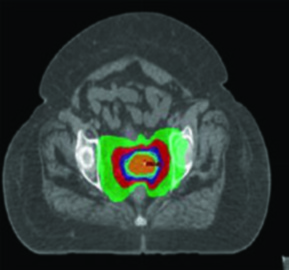

A terapia com prótons pode ser considerada como alternativa de boost para pacientes que não podem receber braquiterapia. Prótons apresentam vantagens dosimétricas em bexiga, intestino, cabeças femorais e reto em comparação ao VMAT. O CTV de boost pode ser determinado por RM obtida após 3 semanas de quimiorradiação, administrando-se então 30 Gy/Gy equivalente em 5 frações em substituição à braquiterapia. Entretanto, evidência prospectiva de alta qualidade ainda é insuficiente, e a relação entre dosimetria melhorada e redução clinicamente significativa de toxicidade permanece sem comprovação definitiva.

SBRT para Câncer Cervical

No câncer cervical locorregionalmente avançado, o padrão de tratamento combina EBRT fracionada diária com cisplatina concomitante seguida de boost com braquiterapia, alcançando dose EQD2 final de 80 a 95 Gy no alvo. A SBRT surge como modalidade especializada que entrega doses altas em 1 a 5 frações, exigindo visualização precisa do alvo, delineação acurada de tumor e OARs, e posicionamento de alta fidelidade com guia de imagem.

Os linfonodos podem receber boost com SBRT. A técnica também se aplica ao cenário de reirradiação para doença recorrente ou tratamento de sítios limitados de metástase. Algumas pacientes não são candidatas à braquiterapia por comorbidades graves, e outras recusam o procedimento — incluindo pacientes em risco de transtorno de estresse pós-traumático.

A SBRT permite entrega conformal de boost em alta dose, mas resultados recentes exigem cautela. Um ensaio fase II investigando SBRT (28 Gy em 4 frações) como substituto da braquiterapia foi encerrado prematuramente por toxicidade maior que a esperada e taxas de controle local, sobrevida livre de progressão e sobrevida global inferiores ao previsto em 2 anos. Braquiterapia permanece o padrão de tratamento para pacientes elegíveis.

Para pacientes que definitivamente não receberão braquiterapia, um esquema de 5 frações (por exemplo, 27,5 Gy em 5 frações) após 45 Gy na pelve pode ser considerado, resultando em EQD2 de 80 Gy (α/β = 10). A determinação de dose e fracionamento deve considerar o tamanho do alvo, RT prévia na área e tolerância dos OARs adjacentes. Para regime de 5 frações, a dose por fração situa-se tipicamente na faixa de 4 a 8 Gy, embora frações de 8 a 15 Gy também tenham sido reportadas. A EQD2 total deve ser calculada para a área tratada. Para entender melhor a SBRT em outros cenários, confira nosso artigo dedicado sobre SBRT em cabeça e pescoço.